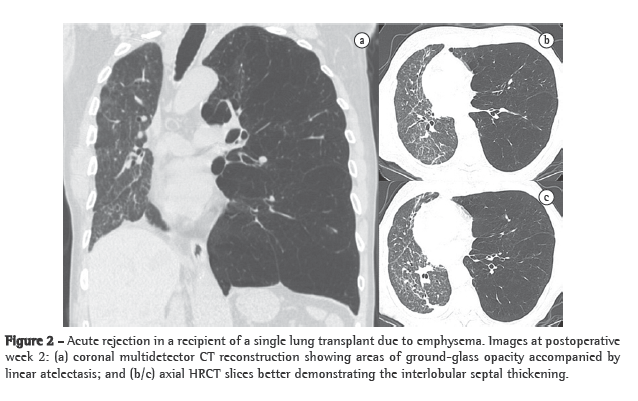

Acute rejection

Acute rejection after transplantation is a common occurrence. Nearly 95% of patients present at least two episodes within the first month after surgery. Histologically, acute rejection is characterized by predominantly lymphocytic perivascular infiltrate, with or without bronchiolar involvement.(8) Symptoms are generally nonspecific, including low-grade fever, breathlessness and fatigue. Most patients experience at least one episode of acute rejection within the first 3 weeks and remain at high risk for this complication for the first 100 days after transplantation.(5) Chest X-ray findings are normal in up to 50% of cases.(6) The most common findings are perihilar and lower-lobe opacities, as well as interlobular septal thickening and pleural effusion (Figure 2).(9) The HRCT features are relatively nonspecific and include ground-glass opacities (often with basal distribution), peribronchial cuffing, septal thickening (interlobular and intralobular) and new or more extensive pleural effusion.(10) This complication can be almost completely excluded if there are no ground-glass opacities.(9) Acute rejection is treated with intravenous corticosteroids and typically responds quite well after 24 h of this treatment. A dramatic reduction in abnormal radiological features after 48 h of intravenous administration of methylprednisolone is indicative of a diagnosis of acute rejection.(9,10)